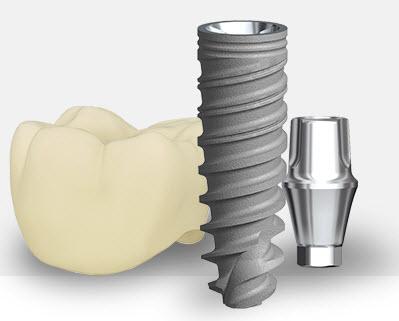

There will be a few months’ wait after implantation so there can be osseointegration, or joining of the jawbone and implant. A crown is placed to rebuild appearance and functionality after the implant is placed, so a natural-looking tooth is restored.

It’s possible to place a prosthetic tooth in an immediate loading dental implant a week after implantation, according to current method. Less time for treatment and earlier aesthetic appearance reconstruction are a couple of the benefits of this course of action. Clinical trials have demonstrated that comparable patient-reported outcomes may be obtained from both immediate and conventional loading practices.